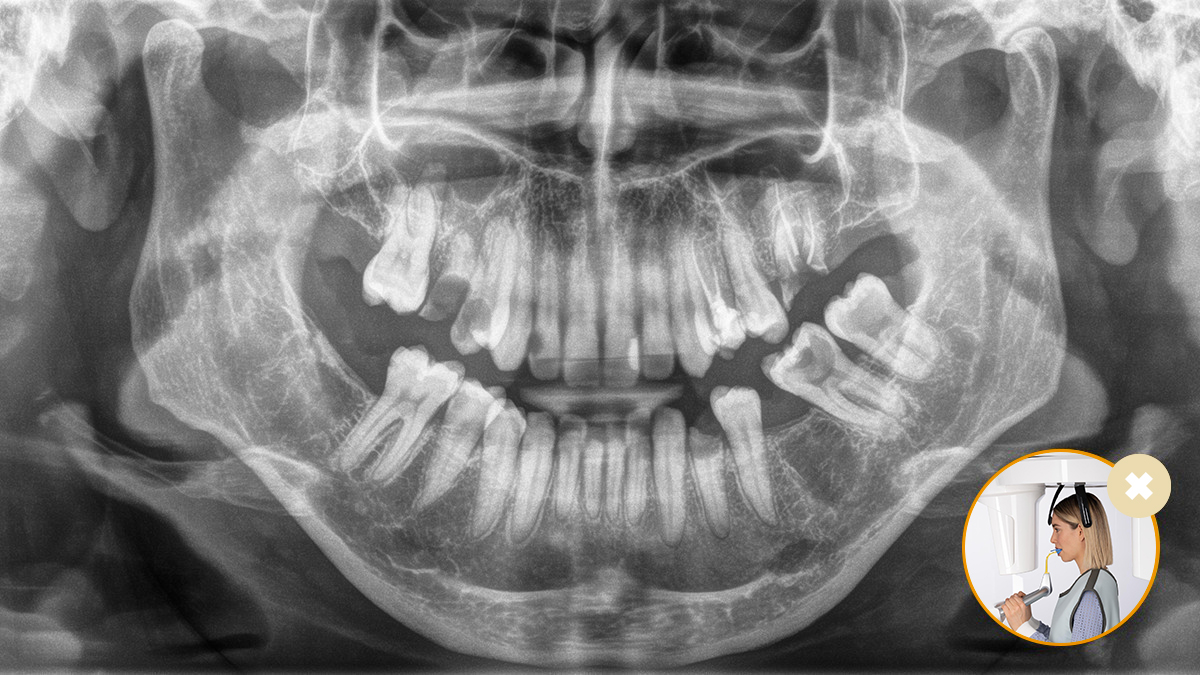

Il corretto posizionamento del paziente porta a un’elevata qualità dell’immagine per supportare una diagnosi accurata e facilita e migliora l’esperienza del paziente.

Questo è il nostro concetto a 10 punti per facilitare il posizionamento del paziente e l’acquisizione di immagini radiografiche. Si tratta principalmente di due cose: alta qualità dell’immagine e comfort per il paziente e l’assistente.